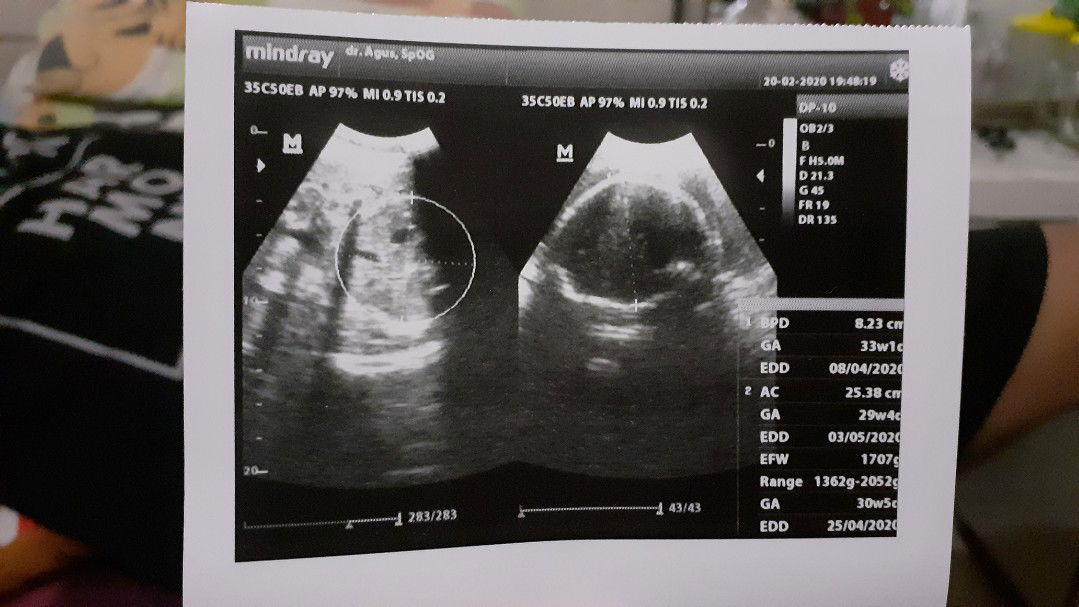

Berat janin

Hallo bun, mau tanya" nih... Usia kandunganku 7 bulan menurut Hari terakir aku haid ya, tapi klo menurut USG itu udh 8bulan mungkin karna ngukurnya dari lingkar kepal dan BB ya bun Yang aku aku tanyain apa wajar diumur 7 bulan berat bayiku segitu.?? Aku takut karan aku seting makan manis dan minum es yang menjadi penyebabnya bun.

Berat bayi saat USG

Hay bu menurur usg usia kandunganku 22wek dan berat baby 601, apa kan segitu normala bun.??